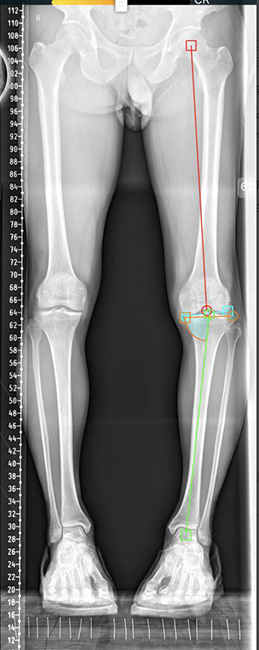

随着病程进展,X片检查会显示关节间隙变窄,边缘骨赘增生,内外侧间隙不对称,导致膝关节内翻或者外翻,通常膝内翻发生率又高于外翻。膝关节内翻或者外翻后,下肢轴线呈现“偏心”,就导致了膝关节内侧间室或外侧间室的高压,其中内侧间室高压情况占90%以上,随着压力增高,压力高的一侧磨损及退变加剧,反过来又加速骨关节炎进展。

术前下肢内翻畸形

据了解,近年来膝关节周围截骨纠正力线手术在临床治疗上取得了较好疗效。经过截骨纠正力线术后,很多患者病程进展快速延缓,甚至能够避免发展到终末期而采取膝关节置换。一般来说,根据患者畸形产生的部位不同,对该疾病可采取的手术方式有:股骨远端截骨(DFO)及胫骨高位截骨(HTO),术前测量偏移度数、周密计算需要纠正的度数,手术中按照术前规划结合透视确认,将偏移的力线恢复到正常生理状态。手术后,膝关节内外侧间室压力重新分配,消除了原来的单侧间室应力集中情况,从而达到治疗目标。手术后次日即可扶拐杖保护下床行走,一月多能丢拐杖行走。